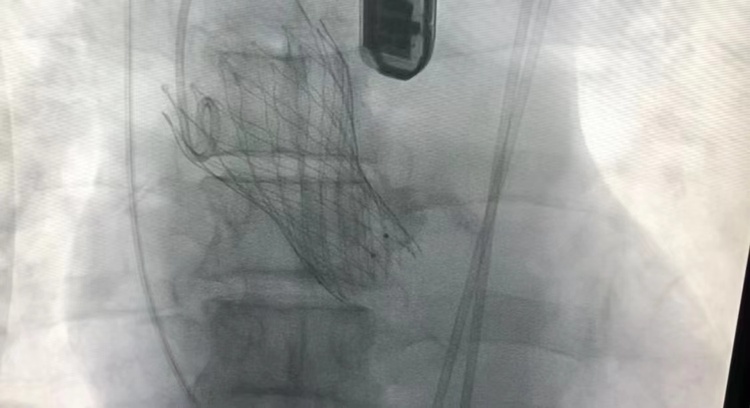

图一:安放支架过程中

图二:支架释放后,心率血压平稳

图三、图四:人工瓣膜成功植入后影像